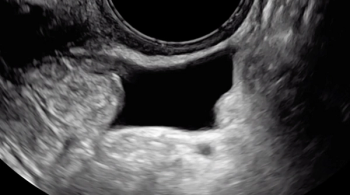

The uterine fundus is being pushed cephalad by the transvaginal ultrasound probe, eliciting smooth sliding of the uterine fundus over the bowel. Some fluid is noted within the rectouterine pouch, which often suggests a non-obliterated pouch.

In this case, there is a fixed ovary posteriorly and subtle hypoechoic nodule posterior to the uterus at the level of the internal cervical os, suggesting of deep endometriosis of the torus uterinus.